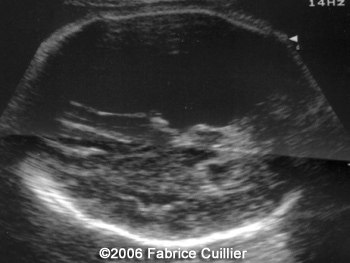

The following images are obtained in a 3rd trimester fetus:

The final diagnosis was: Arachnoid cyst